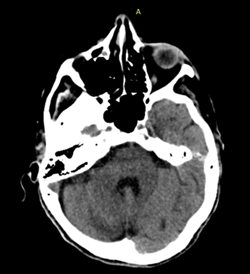

El primero de todos es la asimetría ventricular, caso en el que observamos a un ventrículo de mayor tamaño respecto al contralateral sin que esto signifique hidrocefalia. Esto lo podemos corroborar al identificar las astas temporales de similar tamaño.

Fig. 1.

El segundo error habitual puede producirse ante la presenta de una coartación ventricular. Esto consiste en un contacto de las paredes ependimarias sin valor patológico suele ser confudnido con lesiones con efecto de masa.

Fig. 2.